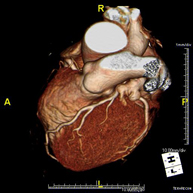

- Coronary CT angiography or Coronary CT

The Coronary CT angiography or non-invasive Coronarography is a diagnostic test to examine arteries of the heart, or coronary arteries, using state-of-the-art MDCT equipment and an iodinated contrast agent to obtain two- and three-dimensional images. Multidetector computed tomography (MDCT) entails high-speed imaging that is beneficial in assessing coronary arteries with high anatomical precision, particularly in evaluating narrowing or stenosis, calcifications, anatomical variants, etc., as its speed prevents the artefact caused by the constant movement of the heart (1,000 images can be obtained in less than 10 seconds). The information obtained requires processing at workstations equipped with specialised software capable of reconstructing the coronary arteries, thereby enabling an assessment to be made of the number, location and characteristics of the lesions. All this information is obtained non-invasively, involving a simple puncture of a peripheral vein (in the arm). To ensure the heart rate stays below 75 bpm, some patients will need preliminary treatment with beta blockers.